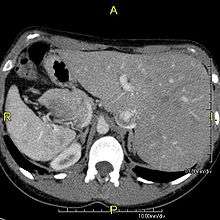

Axial CT image showing situs inversus (liver and IVC on the left, spleen and aorta on the right) in a patient with Kartagener syndrome.

The condition affects all major structures within the thorax and abdomen. Generally, the organs are simply transposed through the sagittal plane. The heart is located on the right side of the thorax, the stomach and spleen on the right side of the abdomen and the liver and gall bladder on the left side. The heart's normal right atrium occurs on the left, and the left atrium is on the right. The lung anatomy is reversed and the left lung has 3 lobes while the right lung has 2 lobes. The intestines and other internal structures are also reversed from the normal, and the blood vessels, nerves, and lymphatics are also transposed.